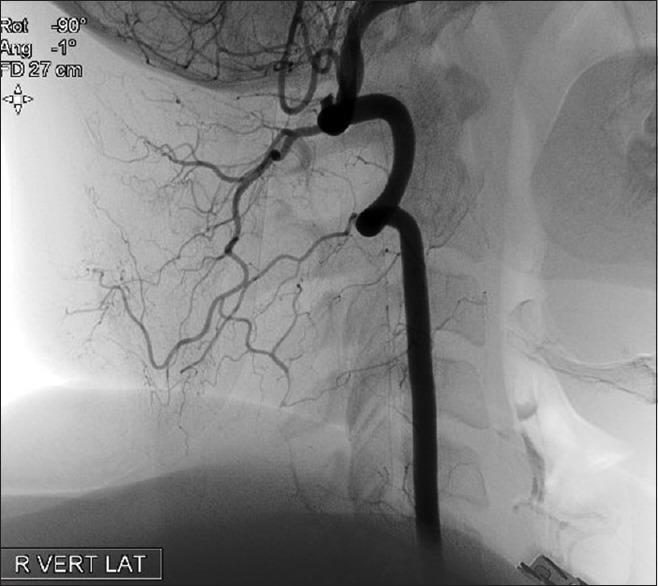

Bow hunter's syndrome (BHS) is characterized with repeating paroxysmal vertigo, nystagmus and ataxia caused by mechanical compression of the vertebral arteries. There is no definite diagnostic and treatment protocol. 26-year-old female patient admitted to the outpatient clinic with complaints of dizziness and seldom falls. Stenosis in the right vertebral artery at the level of C1 and C2 was discovered by the diagnostic modalities. In our patient, we first performed hemilaminectomy by posterior approach. But the symptoms of the patient did not recede, thus we performed decompression with the anterolateral approach by opening the foramens atlas and axis without disrupting the dynamics of the vertebrae and without the need for stabilization. The symptoms of the patient disappeared after this intervention. The patient had complete relief of symptoms at the first year follow up. Surgery must be planned to preserve the life quality of the patient and relieve complaints of the patients. To achieve these goals anterolateral approach must be tried before attempting posterior stabilization.

摘要

弓猎综合征(BHS)的特征是由椎动脉机械性压迫引起的反复阵发性眩晕、眼球震颤和共济失调。目前尚无明确的诊断和治疗方案。一名26岁女性患者因头晕和偶尔跌倒的主诉到门诊就诊。通过诊断手段发现其C1和C2水平的右侧椎动脉狭窄。在我们的患者中,我们首先采用后路进行半椎板切除术。但患者症状并未缓解,因此我们采用前外侧入路,打开寰椎和枢椎的椎间孔进行减压,既不破坏椎体的动力学结构,也无需进行固定。此次干预后患者症状消失。在第一年的随访中,患者症状完全缓解。必须制定手术方案以维持患者的生活质量并缓解患者的症状。为实现这些目标,在尝试后路固定之前必须先尝试前外侧入路。